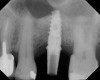

As with implant placement in general, use of a round bur is the first step in forming the osteotomy. As described above, to get verification of positioning—especially if a surgical stent is not used—a small piece of gutta percha can be placed inside this small osteotomy and a radiograph taken (Figure 1), after which the gutta percha is removed. The next step is the most critical, as it involves exposing the Schneiderian membrane. A 2-mm twist drill is used at a speed not exceeding 250 rpm, using a very light touch. Because the bone quality in the maxillary posterior is generally poor, it is usually easy to feel when the medullary bone has been breached and the dense cortical bone of the floor of the sinus has been reached. The cortical plate of the floor of the sinus should have been carefully measured with periapical radiographs presurgically, but it is usually about 1 mm in thickness. The most important and technique-sensitive part of this procedure is breaching the cortical plate of bone lining the sinus without tearing the sinus membrane. With a solid finger rest, good control, very light drilling pressure, copious irrigation, and a slow drilling speed, a slight “give” occurs once this plate of bone is breached. The full width of the twist drill should not penetrate the sinus floor; otherwise, the membrane will be torn. If it is not clear whether the membrane has been exposed, a flat-ended implant probe (Figure 2) can be used by inserting it into the osteotomy and feeling for the slight “give” or movement of the membrane. If the surgeon is not sure if the membrane is exposed, a radiographic marker can be used (Figure 3). If the membrane is significantly exposed, however, a radiographic marker should not be used, as this can inadvertently tear the membrane. The patient should also be warned not to bite down on the marker during the radiograph to avoid a membrane tear, and floss must be attached to the marker, so it can be retrieved if necessary.

Because the bone grafting materials used in this technique need physical stability during healing to support the raised membrane, there is a high probability that significant shrinkage of the graft will occur as it heals and matures if only non-demineralized material is used. For these reasons, a composite graft using calcium sulfate, DFDBA, and mineralized particulate bone is used. A 50:50 mixture by volume of mineralized bone grafting material and DFDBA is used, to which approximately 40% calcium sulfate by volume is added. A higher percentage of calcium sulfate is used relative to that described for composite grafting in other uses, because some of the calcium sulfate will wash out during bone packing. Another advantage to this composite graft is that it is not as radiopaque as a purely mineralized graft. This allows radiographic monitoring of the bone healing around the implant, which can be used to time abutment placement on the implant. This is demonstrated in Figure 4 and Figure 5, which are radiographs taken on the day of the initial surgery showing the radiographic appearance of the composite graft, implant, and graft, and in Figure 6, a 5-month postoperative radiograph with the abutment in place. The old floor of the sinus is indistinguishable from the area of new bone. Figure 7 shows a CBCT scan (Carestream Dental, www.carestreamdental.com) taken at 4 months with the old floor of the sinus indistinguishable from the new bone formed.

After about seven or eight cycles, a radiograph should be taken to verify the apical position of the sinus membrane (Figure 4). If the sinus has been raised at least 3 mm to 4 mm, the 2.8-mm twist drill should be used to remove the remaining bone at the base of the osteotomy. The osteotomy should then be widened to the final twist drill but not yet the last drill, which is the profile drill. This will allow for easier bone tapping into the sinus. The desired height of sinus membrane elevation should be such that there is about 1 mm to 2 mm of additional apical height above the implant to be placed. Usually a 10-mm implant length is sufficient. The design of the implant should have threads close to the coronal aspect of the rough surface for better initial fixation. When using a tapered implant design, the final drill is a tapered profile drill, which is the last step before placing the implant. Because it is slightly longer than the actual implant, its use could tear the membrane. To minimize the chance of tearing the membrane, a high-speed round bur and copious irrigation can be used to flatten the end of the tapered profile drill by about 1.5 mm (Figure 9) before its use. It should be used at less than 200 rpm with limited irrigation. The groove on the profile drill corresponds to the level of the bone when used. If there is minimal native ridge height, the drill should be used to a lesser depth than the groove to make sure that the site is not drilled too deeply.

A 74-year-old man presented with only about 2 mm to 3 mm of native bone below the sinus in the No. 14 position (Figure 13). The composite graft used was an approximately 50:50 mixture of DFDBA (Bio-Oss®, Geistlich Biomaterials, www.bio-oss.com) with the addition of about 40% calcium sulfate by volume (Figure 14). The implant placed (Figure 15) was a 10-mm long, rough-surfaced, platform-shifting implant (tapered 4.2 mm to 2.8 mm), and the sinus was raised about 8 mm. The postoperative radiograph taken at 4 months (Figure 16) showed some shrinkage of the graft, but no demarcation of the old sinus floor in the area.